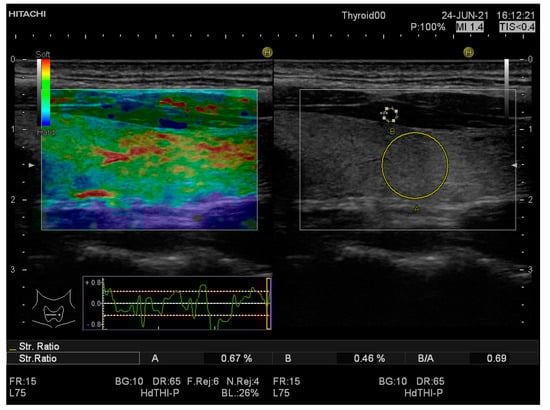

| SR mean value | 1.19 ± 0.25 | 0.68 ± 0.2 | <0.0001 |

| SR-LTL | 1.20 ± 0.31 | 0.66 ± 0.19 | <0.0001 |

| SR-RTL | 1.18 ± 0.27 | 0.70 ± 0.24 | <0.0001 |